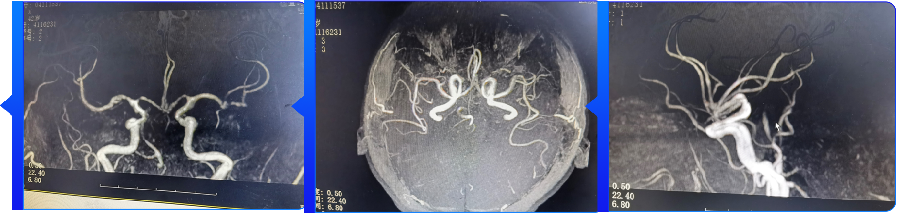

颅脑MRI+MRA(2021.12.04)提示:左侧小脑、脑干急性期脑梗死;基底动脉闭塞。